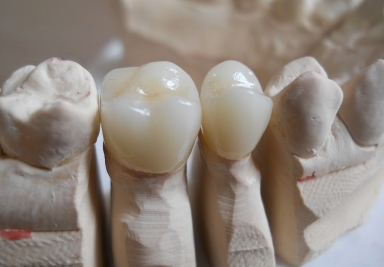

Full ceramic crowns

Full ceramic crowns on upper second premolar and first upper molar